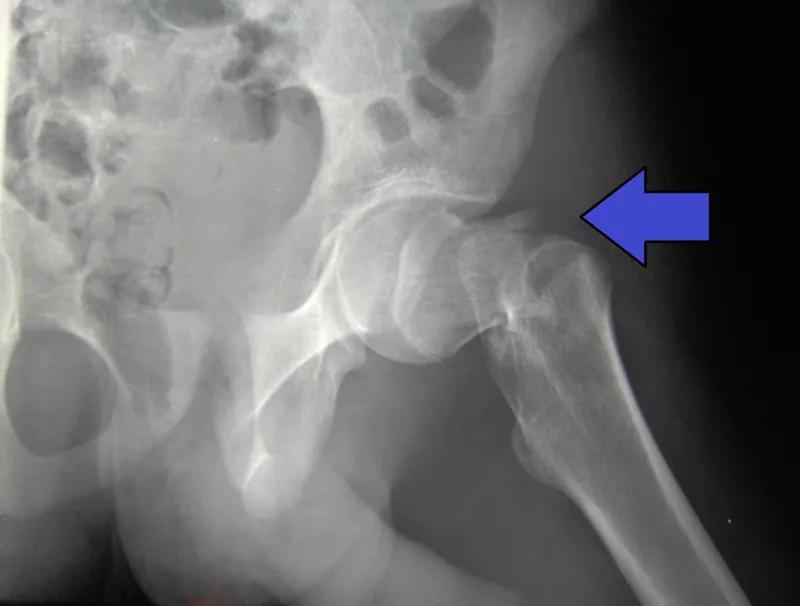

Garden Classification (Intracapsular)

- Type I: Incomplete/impacted (undisplaced)

- Type II: Complete but undisplaced

- Type III: Complete, partially displaced

- Type IV: Complete, fully displaced

- Types III-IV have highest AVN risk (30%)

✓ Intracapsular fractures: High AVN risk (disrupted blood supply); displaced → arthroplasty; undisplaced → internal fixation

✓ Garden classification: I-II undisplaced (fixation), III-IV displaced (arthroplasty) - higher numbers = higher AVN risk